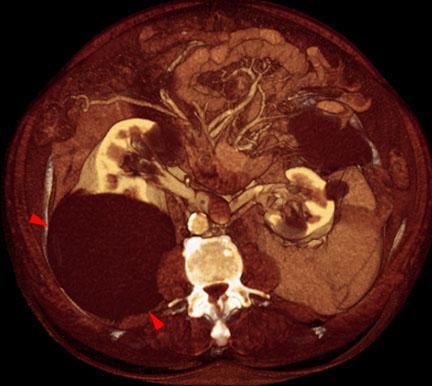

Quiste renal simple

VR seccional. Visión axial caudal. Gran lesión quística (puntas de flecha) en la cara posterior del riñón derecho. En ambos riñones se visualizan pequeños quistes corticales asociados